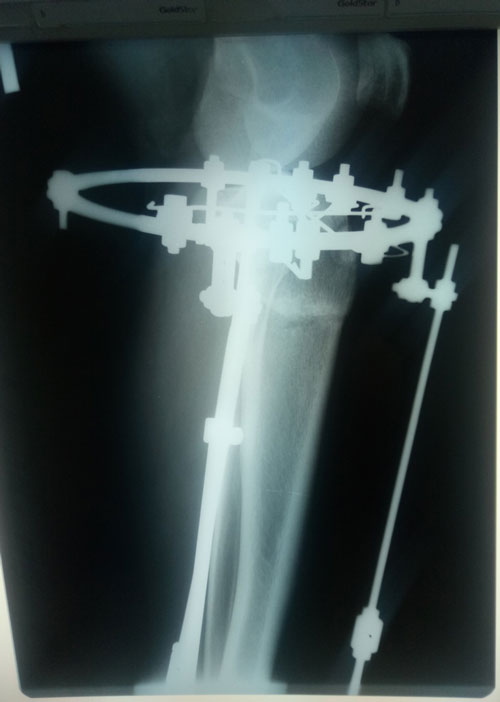

Дата операции- 30.11.2018г.

Дата снятия аппаратов - 12.03.2019г.

Срок сращения - 100 дней.